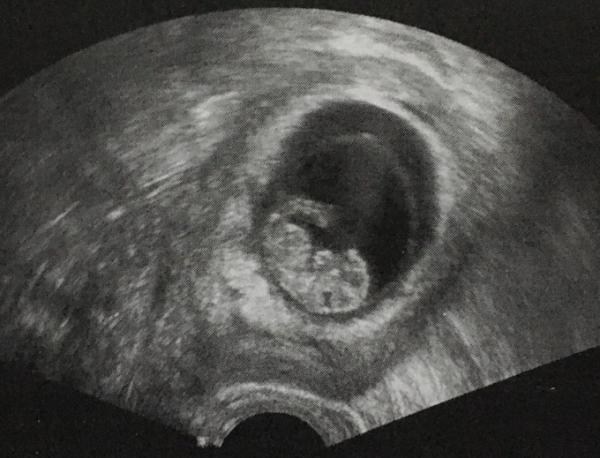

Ich hatte gerade meinen ersten Termin und durfte meinen kleinen Krümel sehen Er hat sich bewegt und das Herz hat schön geschlagen Alles gut und mit einer Größe von 2 cm zeitgerecht. Ich bin mega happy

Bild zu Überglücklich 😍 - Forum für Juli - Mamis